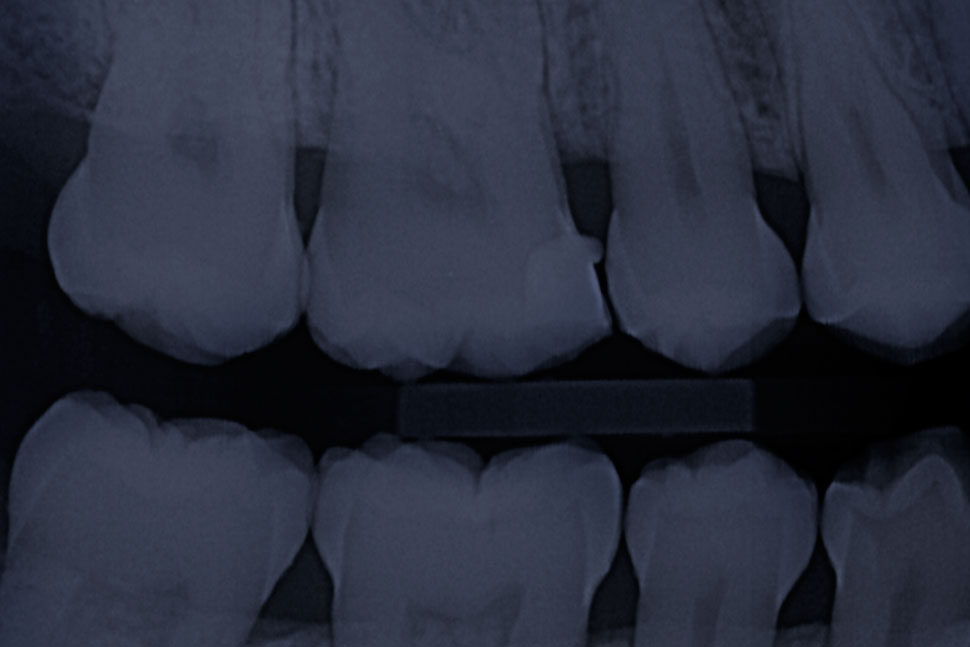

Radiografía Interproximal

Muestra las porciones de la corona de los dientes superiores e inferiores.